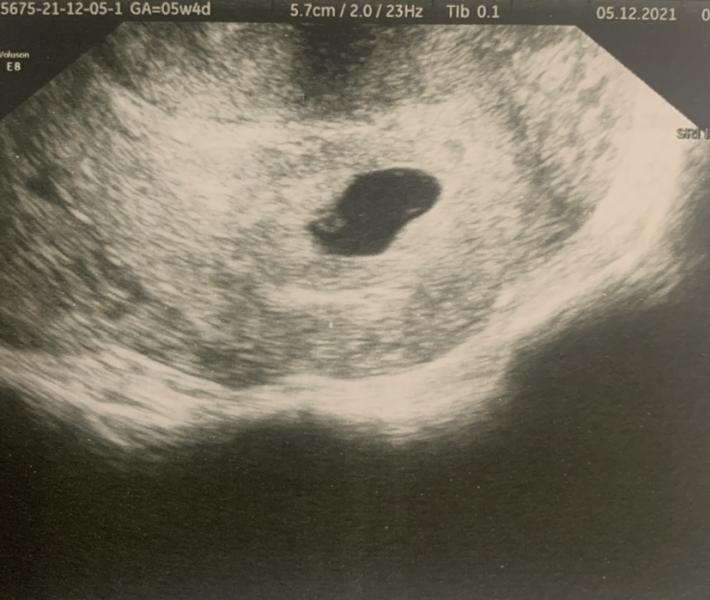

День первого УЗИ после положительного теста и успешного мониторинга уровня ХГЧ с прекрасным приростом. Запись к хвалёному Воронкову в Алмиту. На великолепных эмоциях мы с мужем мчим в клинику, дабы не расписывать того, какая воодушевленная я вошла в кабинет, начну сразу со слов врача:

- Не вижу.

- Что?

- Плодное есть, размеры соответствуют сроку 5 недель 4 дня, эмбриона и желточного мешка не вижу. Под вопросом диагноз.

- Что за диагноз?

- Ставлю предположительно а...